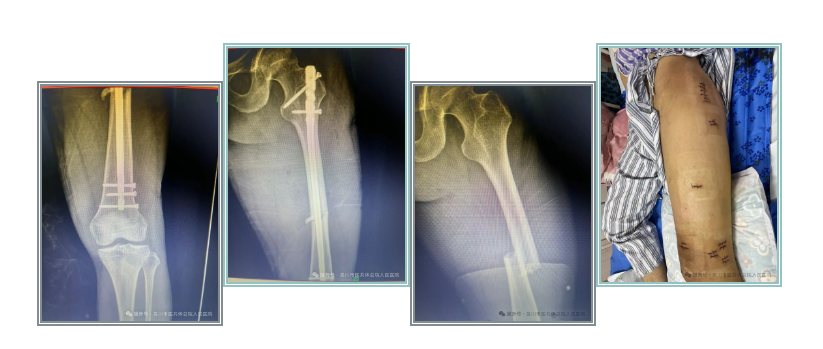

病例四:该患者为78岁老年女性,既往有多发性骨髓瘤病史,外伤致左股骨肿瘤性病理性骨折,完善相关术前准备后,给予左股骨骨折切开复位髓内钉内固定术,减轻了患者痛苦,达早期康复出院。